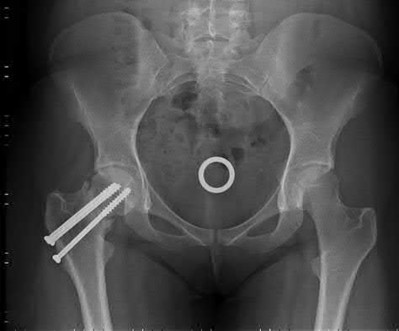

A 76-year-old male community ambulatory presented to clinic complaining of pain in the left groin that has been persistent for the last 8 months. Radiographs obtained from clinic are seen in Figure A. You suspect a femoral neck nonunion and obtain a CT scan which confirmed it. Which of the following statements is true?

A total hip arthroplasty (THA) after nonunion of a femoral neck fracture would provide the best long term outcomes in a 76-year-old male who is a community ambulator.

After nonunion of a femoral neck fracture, hemiarthroplasty and THA are good salvage option for the physiologically older patients. When deciding between these two options, THA is better for active and cognitively intact patients. THA is also indicated in patients with radiographic evidence of degenerative disease about the acetabulum. Hemiarthroplasty is advocated for patients who are older and less active.

Yang et al. retrospectively investigated the risk factors for nonunion in patients treated with cannulated screws. They reviewed 202 patients who had femoral neck fractures and were treated with internal fixation with cannulated screws. They identified that triangle configuration, displaced fracture, borderline or unacceptable reduction, and increased screw shaft subchondral purchase over the femoral neck were all risk factors for nonunion after internal fixation.

Inverted triangle configuration was found to increase rate of union.

Archibeck et al. retrospectively reviewed the outcomes of 102 THAs after failed internal fixation for a hip fracture (including both femoral neck and intertrochanteric). They concluded that the conversion of failed hip internal fixation has elevated risks compared to a primary THA, however, it may still be successful. The biggest concern for these patients postoperatively are periprosthetic fracture and dislocation.

Figures and Illustrations:

Figure A is an AP pelvic radiograph demonstrating a nonunion of a femoral neck fracture after suboptimal fixation with 3 cannulated screws in a triangle configuration.

Illustration A is an AP radiograph of the left hip in this patient following conversion to THA.

Illustration B is a radiograph demonstrating a valgus osteotomy. Illustration C shows an example of a femoral neck nonunion with varus malreduction.